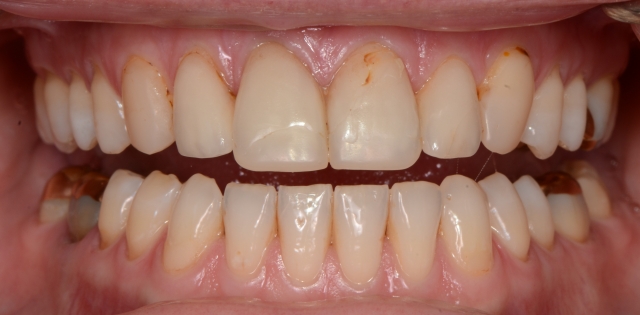

A new patient came to me with this chief complaint: “My front veneers keep breaking. My dentist has fixed them three times, but they keep breaking. I have to travel to Africa in the not-too-distant future and I’m afraid they’ll break again.”

Several interesting discoveries followed. First, I recognized that the teeth were not visible under the lip with the lip at rest.

I also noted that tooth wear was not distributed evenly on the dentition. The lingual aspect of the maxillary anterior teeth looked severely worn.

I pulled out the leaf gauge to confirmed the joints could be loaded, and began progressively decreasing the number of leaves to discover the first point of contact at the seated condylar position. I discovered a posterior initial contact at a significantly open position that deflected the mandible so the mandibular anterior teeth ran into the lingual aspect of the anterior teeth at the very place where her veneers had been breaking.